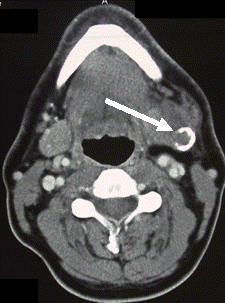

Computertomographie eines verkalkten Speicheldrüsentumors (Pfeil)

In den meisten Fällen reicht eine klinische Untersuchung zusammen mit einer Ultraschalluntersuchung aus. Neue Geräte mit verstellbarer Auflösung und Eindringtiefe (sog. high-end-Geräte) sind dabei inzwischen Standard. Hiermit lassen sich meist sowohl Tumore, Steine und Entzündungen feststellen. Manchmal kann es auch sinnvoll sein, eine Speichelgangsspiegelung (Sialendoskopie, Sialoskopie) durchzuführen, um die Ursache der Beschwerden festzustellen. Nur in seltenen Fällen sind spezielle Untersuchungen wie Kernspintomographie (Magnetresonanztomographie = MRT), Kontrastdarstellung der Gänge (Sialographie), Computertomographie oder Szintigraphie erforderlich. Bei Tumoren kann es sinnvoll sein, bereits im Vorfeld Gewebe mit dünnen Nadeln (Feinnadelaspirationszytologie) oder speziellen Stanzapparaten zu gewinnen und zur Untersuchung einzuschicken.